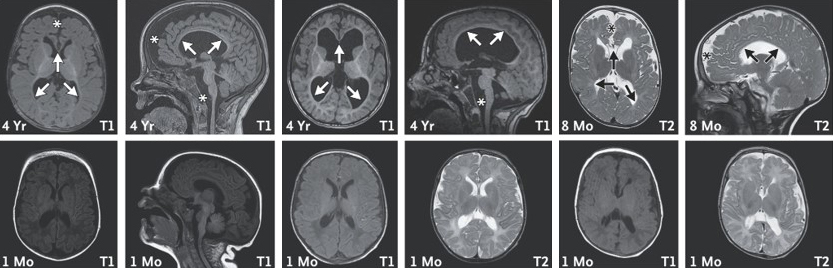

לאחר שנוצר הקשר הראשוני ב-2019, החלו שיחות זום חודשיות בין חוקרים ברחבי העולם ובין בריאן ברודבנט, אביה המסור של אמה. המדענים הדגישו בפניו את הקושי ללמוד ממקרה בודד, אך פריצת דרך חשובה התרחשה ב-2021, כשהתקבל מייל מקבוצת מחקר צרפתית שנתקלה במקרה בילד נוסף שהיה חסר לו עותק של הגן. שנה לאחר מכן, נמצא מקרה שלישי בצרפת, ואף שתחילה נדמה היה שהמקרים אינם דומים, שיחת זום גורלית שינתה את התמונה. "בשיחה השתתפו החוקרים ומשפחות הילדים ונעזרנו בפוסט-דוקטורנטית מצרפת שעבדה בבוסטון שיכלה לתרגם מצרפתית לאנגלית", מתאר פרופ' אוליצקי. "בפעם הראשונה שהמשפחות ראו זו את זו הן זיהו מיד שלילדיהן מאפיינים דומים מבחינה נוירולוגית וגם דמיון פיזי. בדיקות מעבדה הראו כי בתאיהם של הילדים, כמו שראינו בעכברים, מצטברות רמות גבוהות של CHD2. סריקות MRI הראו כי בשנים הראשונות לחיי הילדים ישנה פגיעה מחריפה בחומר הלבן במוח, שאחראי לעדן ולדייק את העברת האותות בין תאי העצב. כעת לכל משפחה יש אבחנה – תסמונת עיכוב שכלי התפתחותי ואפילפסיה הנגרמת מעותק חסר של הגן צ'ייסר – ויש להן גם קשר לעוד משפחות שמתמודדות עם המחלה. ועדיין, לא יהיה סוף טוב לסיפור עד שנמצא טיפול".